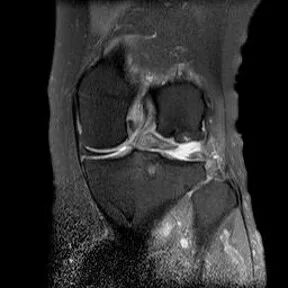

桶柄状撕裂MRI表现

1、宽度减小,在通过半月板体部的冠状面上蝶形消失,同时可见内移的半月板位于髁间窝、交叉韧带旁2、矢状面示残余的前角或后角变小或截断3、半月板前(后)角增宽或双半月板前(后)角征4、双前交叉韧带或双后交叉韧带征

桶柄状撕裂:宽度减小,在通过半月板体部的冠状面上蝶形消失,同时可见内移的半月板位于髁间窝、交叉韧带旁